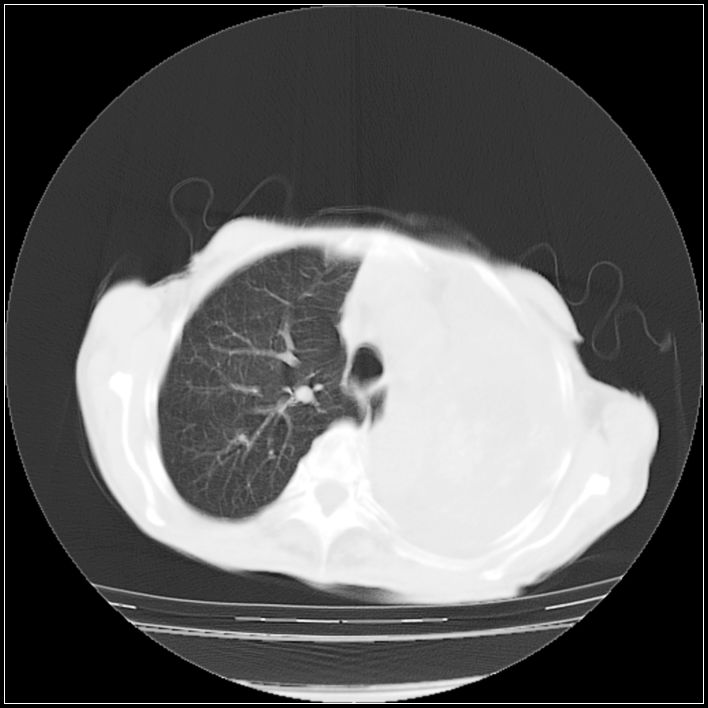

以下是引用ydx_74在2008-5-31 16:08:00的发言:[br]中心性肺癌并左侧肺不张、胸水。

以下是引用影象小辈在2008-5-31 16:25:00的发言:[br]左侧胸腔团状不规则致密影,界欠规整,密度不均匀,其内可见更低密度影及高密度影,并可见包裹性胸腔积液 考虑为1.畸胎瘤 2.肺癌